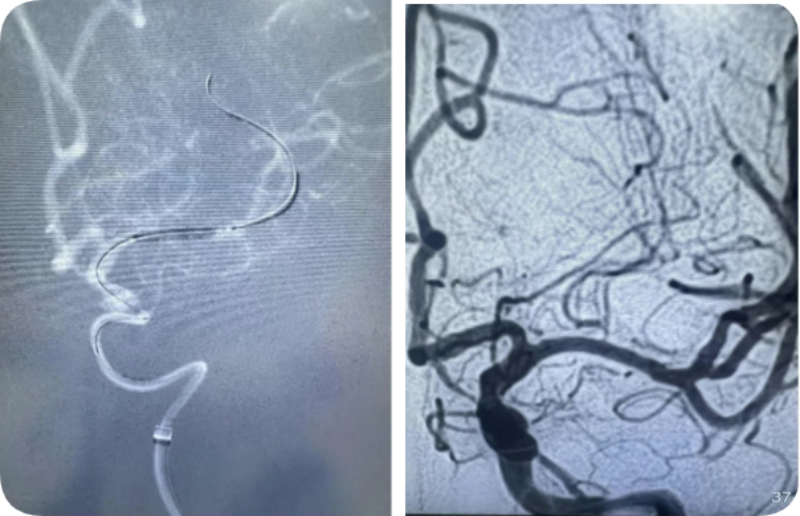

精准操作!在2.25毫米的血管内“起舞”

颅内血管纤细且脆弱,正常血管也只有2.25毫米,在重度狭窄的颅内血管内放置支架是一项严峻挑战。郭宗培、陈历、熊建医生、聂毅医生团队,身披重达15斤的铅衣,操控堪比头发丝样的导丝,球囊适度扩张狭窄血管,精准释放颅内药物涂层支架,使血管狭窄解除,远端血管再次丰富充盈,为减少以后发生脑梗塞的可能性打下坚实基础。整个过程需要团队的团结紧密协作,这场手术考验的是医生的整体医疗素质。